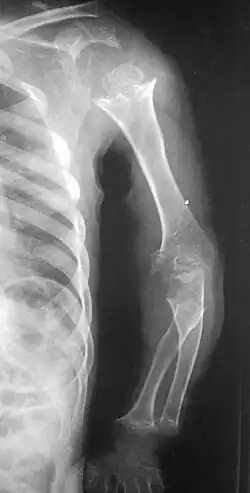

| Pseudoachondroplasia. Shoulders and Humeri. Note the dysplastic proximal humeral epiphyses, metaphyseal broadening, irregularity and metaphyseal line of ossification. These changes are collectively known as "rachitic-like changes". Lesions are bilateral and symmetrical. | |

- Dysplastic/hypoplastic epiphyses especially of shoulders and around the knees.

- Metaphyseal broadening, irregularity and metaphyseal line of ossification. These abnormalities that are typically encountered in proximal humerus and around the knees are collectively known as "rachitic-like changes".

- Radiographic lesions of the appendicular skeleton are typically bilateral and symmetric.